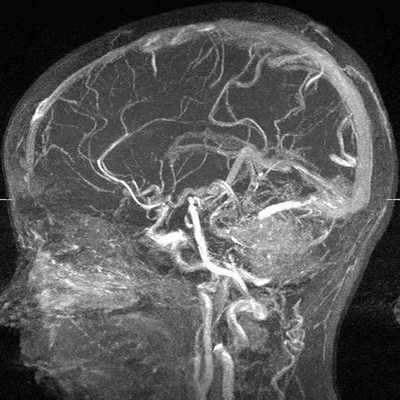

МР-ангиография головного мозга

МРТ или УЗДГ сосудов головы используют для получения изображения артерий и вен и поиска патологии, которая привела к неврологическим симптомам. Методы имеют ключевую разницу в принципе работы.

Магнитно-резонансная томография - высокотехнологичный и безопасный метод диагностики. МРТ головного мозга позволяет определить причину неврологической патологии, в том числе сосудистого происхождения при выполнении МР-ангиографии. В основе метода лежит использование магнитного поля. Последнее возбуждает протоны водорода, которых больше всего в насыщенных водой тканях. Обратный сигнал улавливается датчиками, программа обрабатывает показатели, а врач получает изображение.

Шаг снимков начинается от 1 мм. Тонкие срезы позволяют сделать результат достоверным и информативным. При изучении мозга могут применять МР-ангиографию с контрастом. Проведение усиленного сканирования сосудов даст информацию о наличии:

Наилучший вариант для детальной визуализации сосудов мозга - МРТ головы с ангиографией. Данное исследование имеет определяющее значение в случае, когда подозревают новообразование, аневризму или артерио-венозную мальформацию в обсуждаемой области. Высокая разрешающая способность делает изображения артерий и вен головного мозга более достоверными, чем при сонографии.